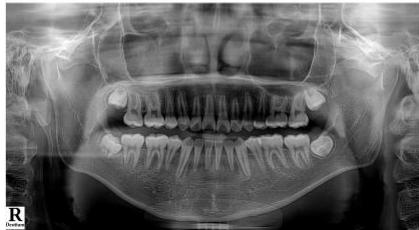

Intraoral examination revealed severe proclination and protrusion of both the maxillary and mandibular incisors [6]. The occlusal relationship was Class I at the canine (tooth 3) and first molar (tooth 6) levels bilaterally. A critical unfavorable biological factor was the proximity of the mandibular incisor roots to the labial cortical plate, representing a high-risk condition when planning extraction-based anterior retraction mechanics [10-12]. All four third molars were present.

Figure 13: Post-Treatment Lateral Cephalometric and Panoramic Radiographs